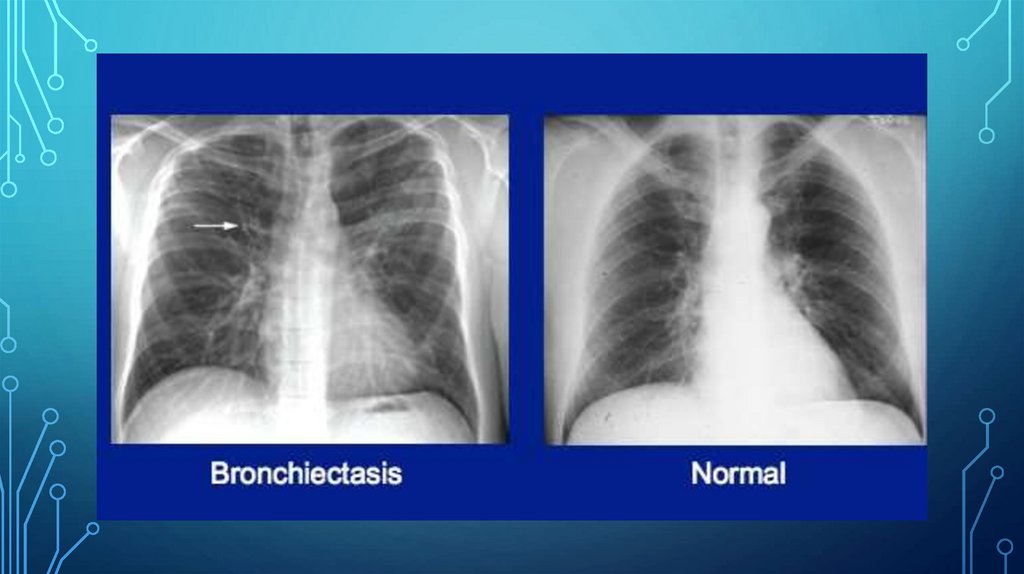

• Рентгенография грудной клетки в двух проекциях: рентгенологические признаки

хронического бронхита или пневмонии;

• Спирометрия: нарушение функции внешнего дыхания по рестриктивному типу;

• КТ органов грудной клетки: распространенные бронхоэктазы.